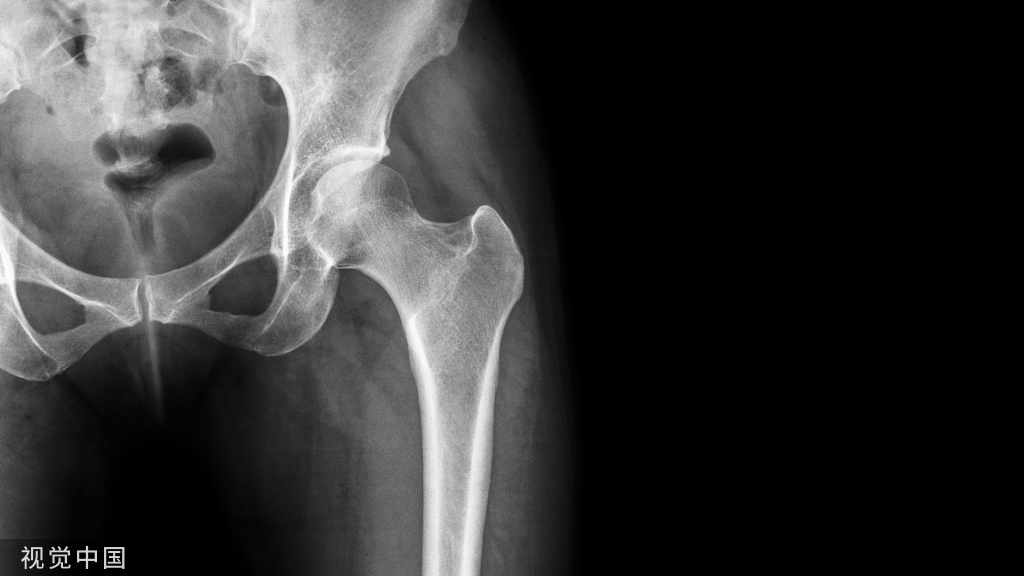

早在上世纪90年代就有人注意到,女运动员的ACL受伤概率比男运动员高出很多,两者相差3〜6倍。(ACL是膝盖前部的两根呈交叉状排列的韧带,可以防止胫骨向前移动,滑出半月板。)有人认为女性的骨盆比男性宽,因此女运动员在落地的时候双膝有内翻的倾向(俗称内八字),这就会让膝盖承受更大的冲击力;还有人比较了男女膝盖的内部结构,发现女性的髁间窝(Intercondylar Notch)比男性要小,当膝盖伸直的时候,ACL就会和髁间窝发生不必要的亲密接触,从而导致受伤。